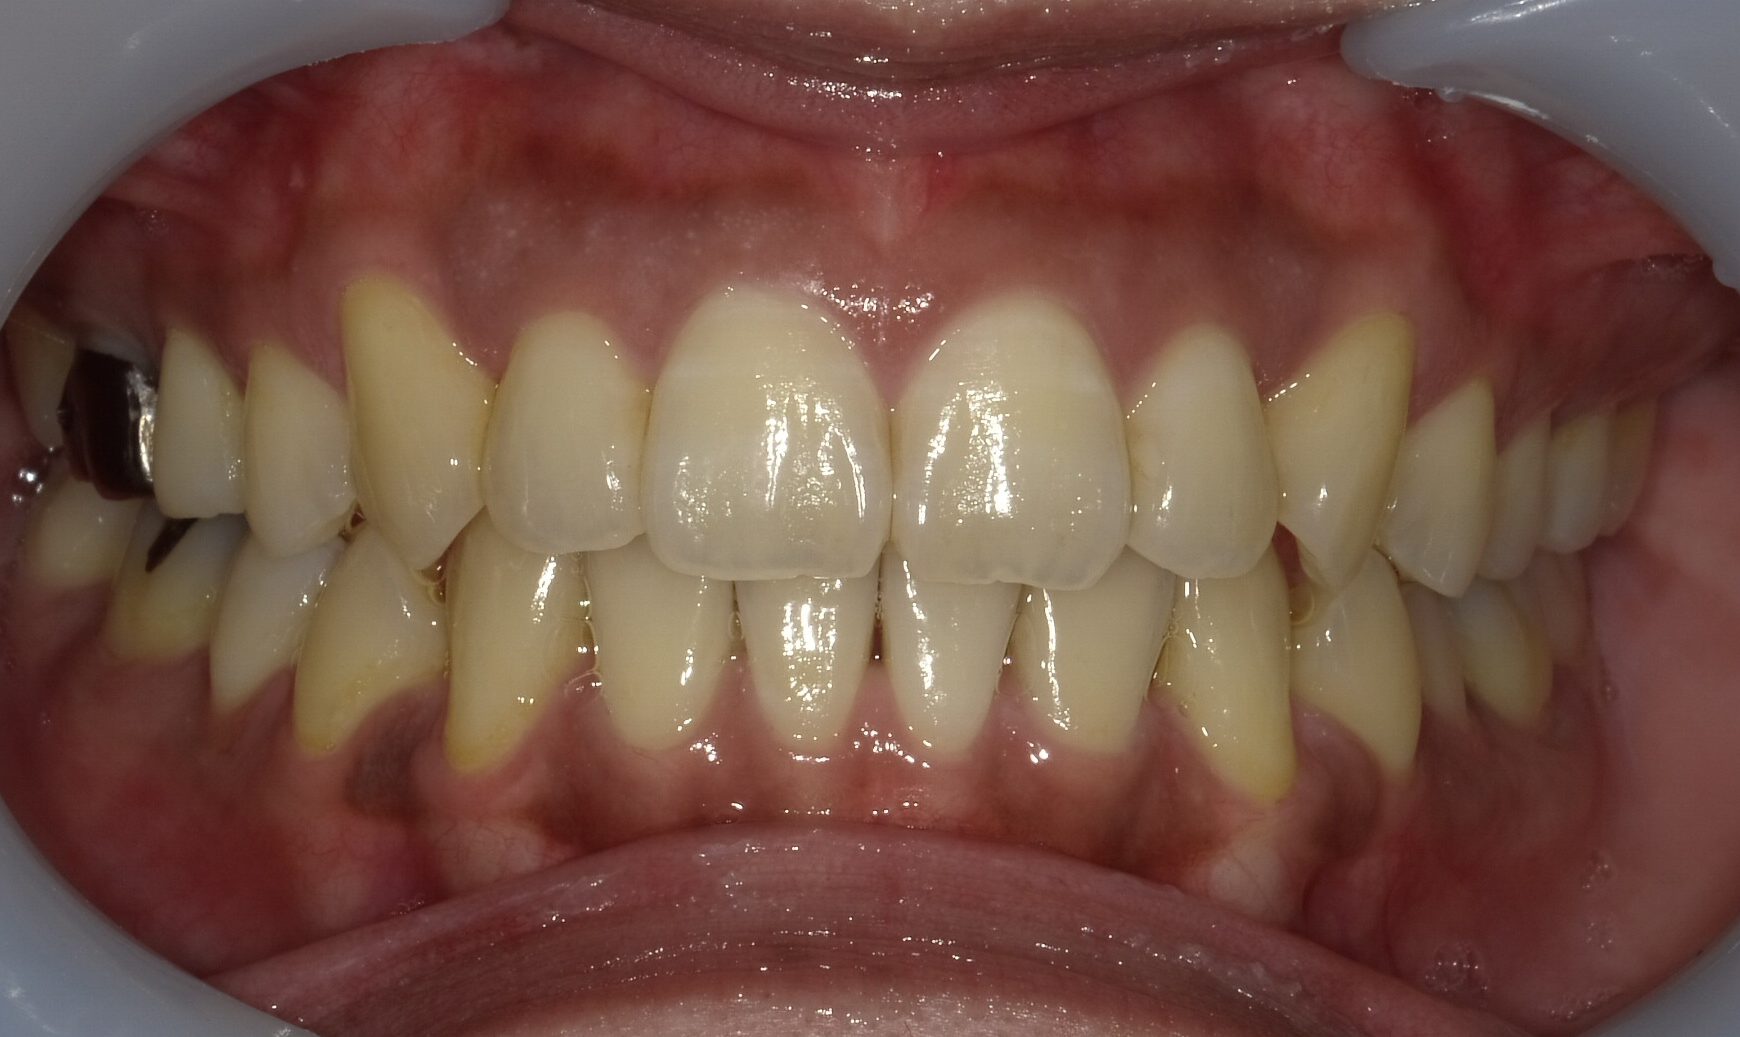

【症例1】重度の叢生(でこぼこ)を非抜歯で改善

「前歯が大きく重なり、他院で4本抜歯が必要と言われた」という30代女性のケースです。

- 治療方法: インビザライン・コンプリヘンシブ上下

- 治療期間: 1年6ヶ月

- 治療費用: 99万円(税込)

- 治療のリスク・デメリット 装着時間を守らないと期間が延長することがある

- ポイント: 抜歯をせずにIPRと遠心移動を組み合わせ、理想的なアーチを実現しました。